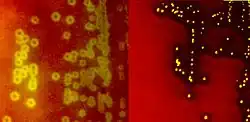

Alpha-hemolytic S. viridans (right) and beta-hemolytic S. pyogenes (left) streptococci growing on blood agar

Species of streptococci are classified based on their hemolytic properties.[10] Alpha-hemolytic species cause oxidization of iron in hemoglobin molecules within red blood cells, giving it a greenish color on blood agar. Beta-hemolytic species cause complete rupture of red blood cells. On blood agar, this appears as wide areas clear of blood cells surrounding bacterial colonies. Gamma-hemolytic species cause no hemolysis.[11]

Beta-hemolysis (β-hemolysis), sometimes called complete hemolysis, is a complete lysis of red cells in the media around and under the colonies: the area appears lightened (yellow) and transparent. Streptolysin, an exotoxin, is the enzyme produced by the bacteria which causes the complete lysis of red blood cells. There are two types of streptolysin: Streptolysin O (SLO) and streptolysin S (SLS). Streptolysin O is an oxygen-sensitive cytotoxin, secreted by most group A Streptococcus (GAS), and interacts with cholesterol in the membrane of eukaryotic cells (mainly red and white blood cells, macrophages, and platelets), and usually results in beta-hemolysis under the surface of blood agar. Streptolysin S is an oxygen-stable cytotoxin also produced by most GAS strains which results in clearing on the surface of blood agar. SLS affects immune cells, including polymorphonuclear leukocytes and lymphocytes, and is thought to prevent the host immune system from clearing infection. Streptococcus pyogenes, or GAS, displays beta hemolysis.

When alpha-hemolysis (α-hemolysis) is present, a blood based agar under the colony will appear dark and greenish due to the conversion of hemoglobin to green biliverdin. Streptococcus pneumoniae and a group of oral streptococci (Streptococcus viridans or viridans streptococci) display alpha-hemolysis. Alpha-hemolysis is also termed incomplete hemolysis or partial hemolysis because the cell membranes of the red blood cells are left intact. This is also sometimes called green hemolysis because of the color change in the agar.